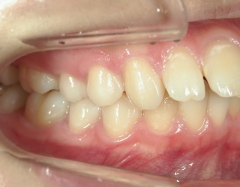

矯正歯科 治療前